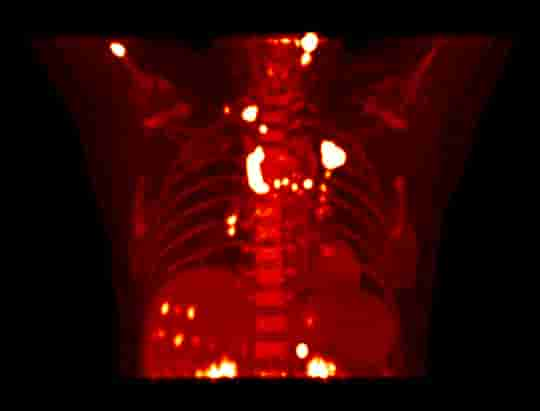

Przejrzystość obrazów uzyskiwanych z użyciem uMI Panorama wykracza poza pojedynczy parametr. System zapewnia wynoszącą 2,9 mm rozdzielczość PET wg NEMA oraz rozdzielczość czasową poniżej 200 ps, a 160-warstwowy tomograf komputerowy wykonuje pełny obrót w czasie 0,25 s z rozdzielczością przestrzenną 0,22 mm, gwarantując wysoką dokładność ilościową i wykrywalność małych zmian.

Zwiększenie możliwości badań klinicznych i obrazowania terapeutycznego oraz diagnostycznego dzięki doskonałej rozdzielczości PET i TK, wysokiej czułości PET, a także platformie sztucznej inteligencji uMI Panorama.